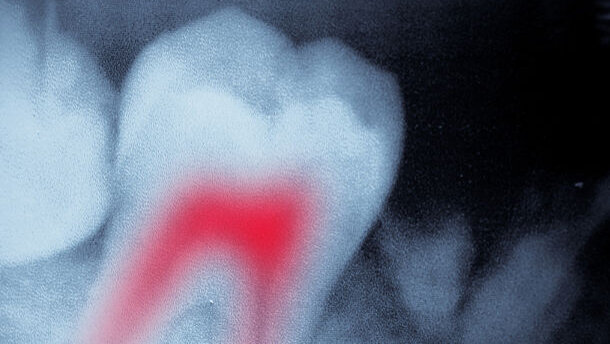

CHICAGO, Ill. & MIAMI, Fla., USA: Tooth pain occurring after endodontic treatment might originate more often from another source than from the treated tooth itself. Having reviewed studies from a period of 60 years, U.S. researchers claim that in six out of ten cases of post-endodontic pain, the cause had nothing to do with the tooth that was treated originally.

In their review published in the December issue of The Journal of the American Dental Association, researchers from the University of Minnesota School of Dentistry analysed 10 out of 770 English-language studies conducted between 1949 and 2009. It was required that treated teeth qualifying for inclusion in the review be followed up for at least six months after treatment.

According to the review, the findings could have serious implications for the diagnosis and clinical management of post-endodontic pain. Dr Paul Benjamin, a dentist from Miami, said in a commentary that was also released by the journal that should the results be verified, almost 700,000 cases of tooth-related pain could be misdiagnosed on an annual basis in the U.S. alone. He advised clinicians to incorporate the new knowledge into future diagnoses of post-endodontic pain and to eliminate other possible sources, including pain associated with the musculoskeletal system or systematic diseases like cancer.

Post-endodontic pain has been identified in latest studies to occur in 5 to 6 per cent of all endodontically treated teeth. Clinical management is usually focused on the treated tooth itself and includes administering pain-relieving medication.